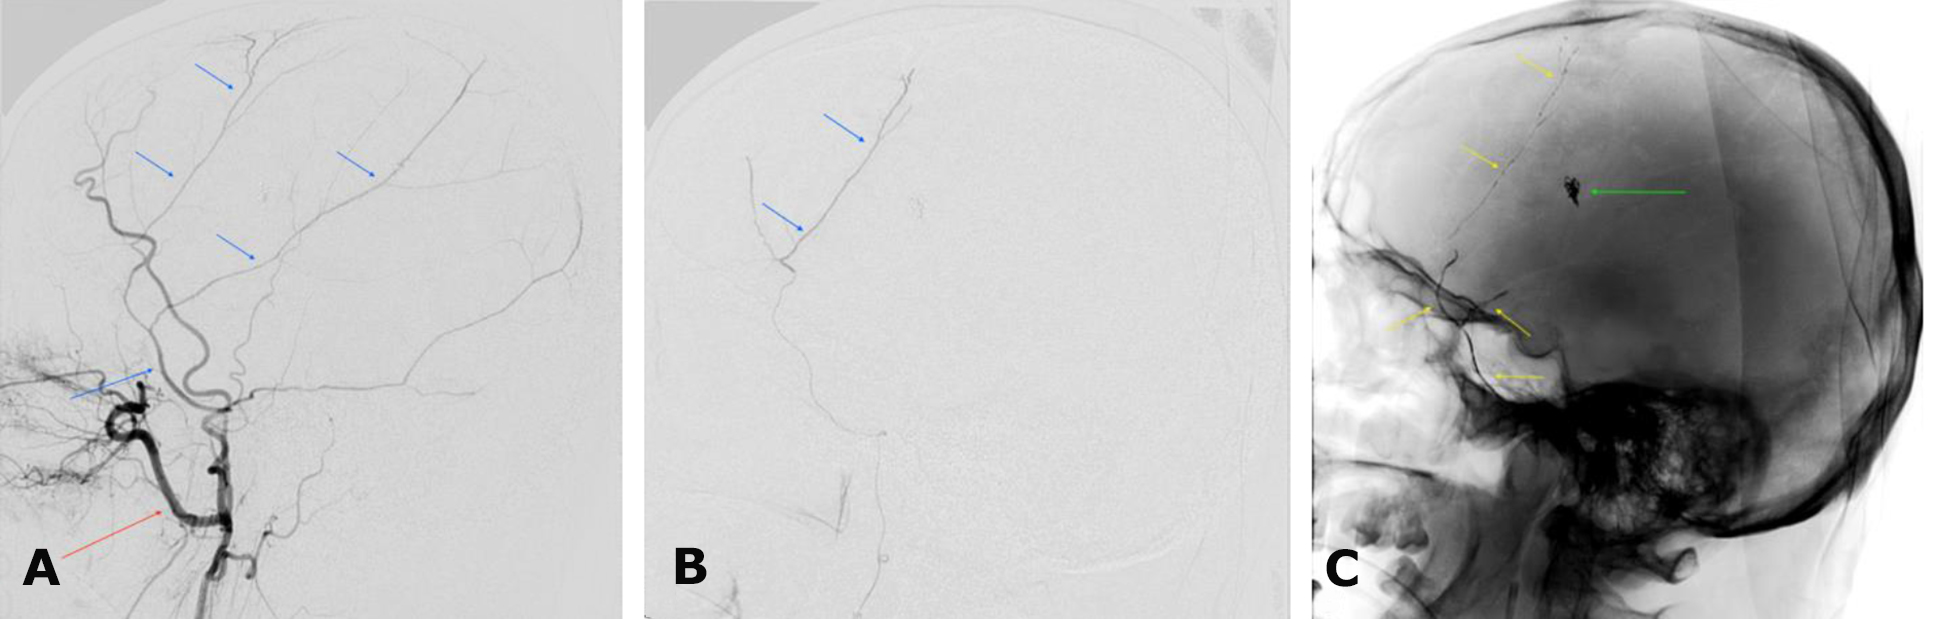

In the same session, X-ray endovascular embolization of the right MMA using the Onyx™ embolic agent was performed on October 3, 2024 (Fig. 8).

Fig. 8. Postoperative cerebral angiography. Right external carotid artery territory: A – subtraction angiogram in the left lateral projection; B – superselective subtraction angiogram of the MMA in the left lateral projection; C – angiogram in the left lateral projection without digital subtraction. The red arrow indicates the maxillary artery; blue arrows indicate the MMA and its branches; the yellow arrow denotes the contrast-enhanced embolization zone of the MMA; the green arrow indicates microcoils in the projection of the mycotic aneurysm

X-ray endovascular embolization of the right MMA using the Onyx™ embolic agent was performed on March 21, 2024 (Fig. 11).

Fig. 11. Intraoperative cerebral angiography. Right external carotid artery territory: A – left lateral projection, arterial phase; B – left lateral projection, arterial phase, superselective angiogram of the right MMA; C – left lateral projection, arterial phase, post-embolization state of the right MMA; D – angiogram in the left lateral projection without digital subtraction. The right MMA and its branches are indicated by a red arrow; the right maxillary artery by an orange arrow; the right external carotid artery by a light blue arrow; the microcatheter positioned within the right MMA by a green arrow; the radiopaque cast of the right MMA after Onyx™ embolization by a yellow arrow; and the hazardous anastomotic branches of the MMA by white arrows: 1—medial; 2—sphenoidal; 3—ramus meningolacrimalis